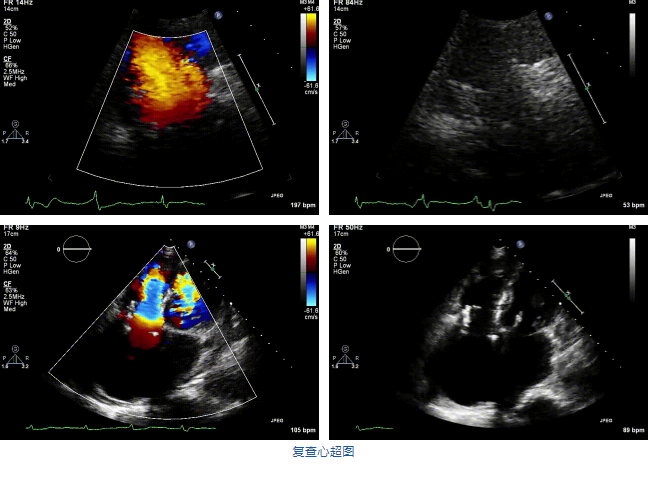

結(jié)合術(shù)前CT評估結(jié)果,葛均波院士團(tuán)隊(duì)最終決定選用LuX-Valve Plus 50mm和55mm兩種型號的瓣膜,并于2021年11月30日順利完成LuX-Valve Plus經(jīng)血管三尖瓣置換術(shù),手術(shù)室即刻拔除氣管插管,術(shù)后第二天轉(zhuǎn)出心內(nèi)科監(jiān)護(hù)室,下床活動(dòng)。術(shù)后患者三尖瓣反流癥狀得到顯著改善,復(fù)查心超結(jié)果顯示人工三尖瓣瓣膜支架固定穩(wěn)定,瓣葉關(guān)閉形態(tài)未見異常,未見明顯反流。